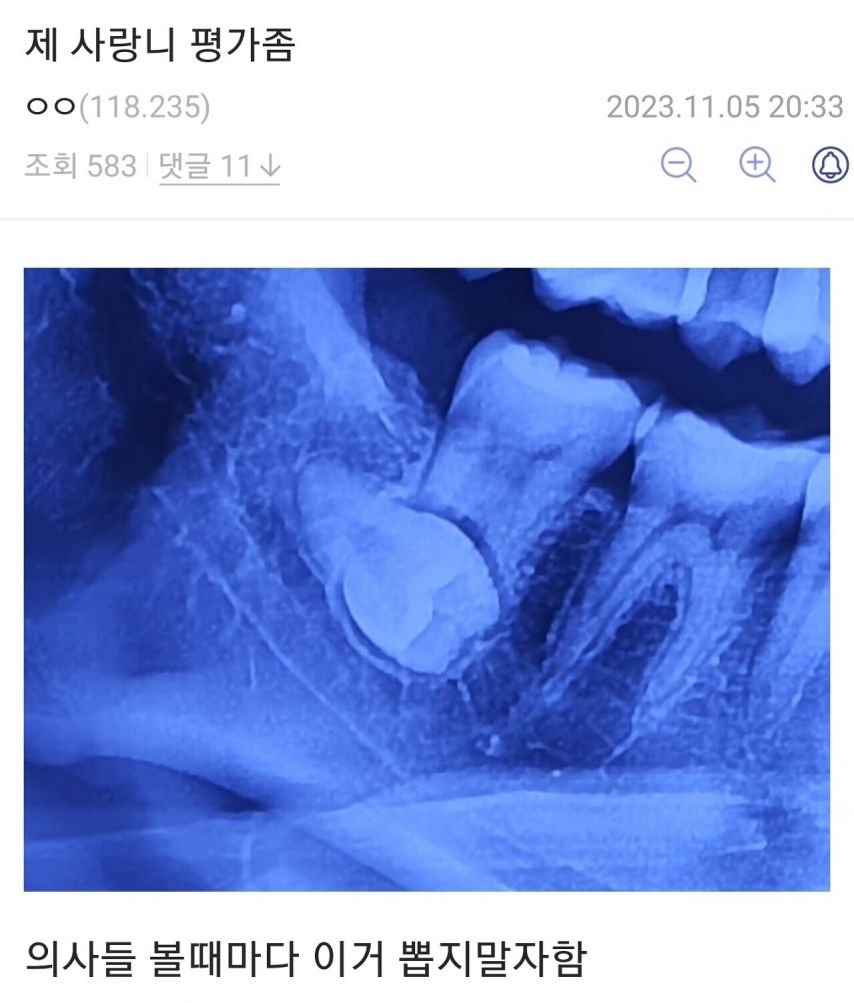

사랑니 평가

달천